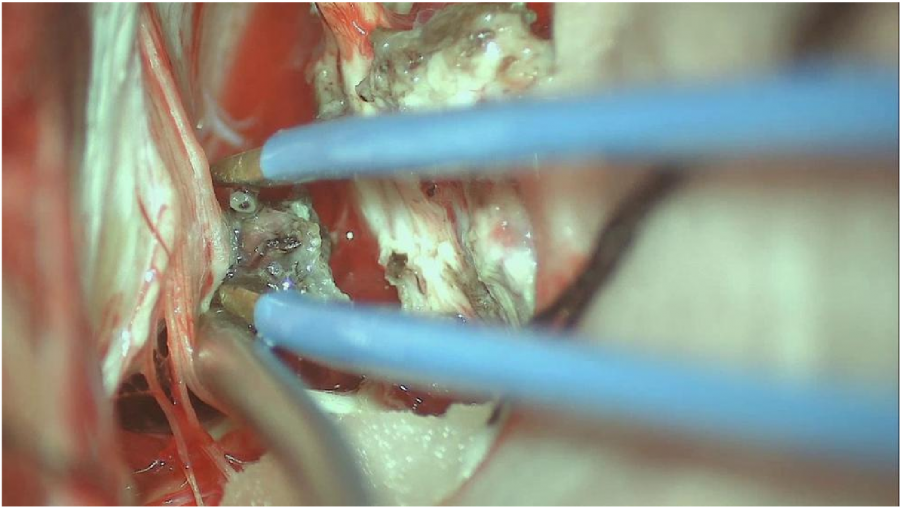

⾏左侧远外侧⼊路脑⼲⾎管畸形切除术,术中所⻅:

3、脑⼲动静脉畸形⼿术切除是注意辨别供⾎动脉与引流静脉,其往往不似其他部位的动静 脉畸形,有叫粗⼤的引流静脉。术中如果不能辨清各⾎管来源与去处,往往会造成不可估量的损失。

4、脑⼲动静脉畸形团周围玩个昂存在复杂的神经及⾎管,操作难度⼤。